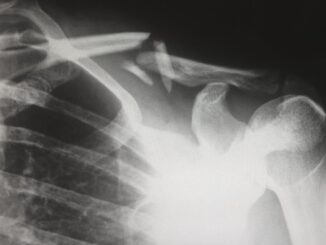

Precision Pediatrics: Children’s Hospital Colorado Forges the Future of Personalized Care In the ever-evolving, sometimes dizzying landscape of pediatric healthcare, precision medicine has truly emerged as a beacon of hope, a guiding light that promises […]